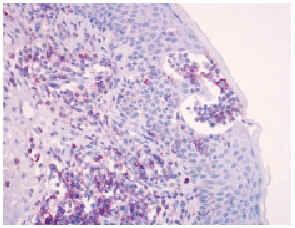

Una biopsia de la piel eritrodérmica mostraba un intenso infiltrado linfocitario pleomórfico, en banda subepidérmica, con epidermotropismo, así como fenómenos dispersos de exocitosis linfocitaria y microabscesos de Pautrier (figs. 2 y 3): el infiltrado linfocitario era positivo para CD4 y CD3, y negativo para CD22 y CD8 (fig. 4). El estudio histológico de una adenopatía mostró una infiltración específica por linfoma.

Fig. 4.--Positividad para la tinción con CD4 y detalle de microabsceso de Pautrier.